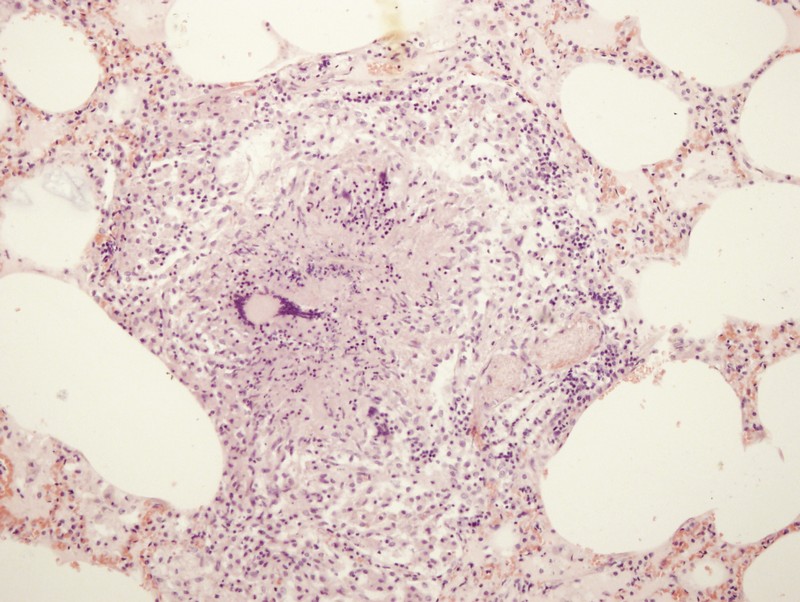

Микроскопический взгляд на мишитарный туберкулез легкого: фотодокументация